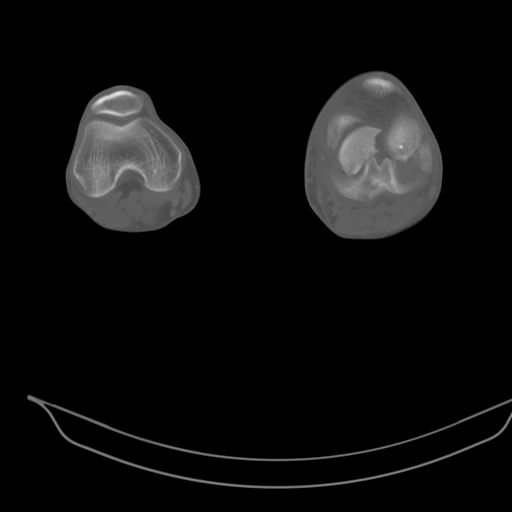

CT shows major bony fragments which are markedly rotated .With this amount of bony damage,you probably should attempt to get reasonably loooking knee with ORIF and thn if he needs a TKR due to pain a few years from now, then tleast you have something looking like a knee that you can replace rather than having to use revision knee for a primary TKR now. 4 weeks is not too long .what is the condition of soft tissues?

При внутрисуcтавных переломах трехмерные (3D) изображения, кроме красивого снимка, не дают полную информацию о состоянии отломков, самыми информативными являются корональные срезы на КТ и обычная длинная ренгенограмма конечности для сравнения оси конечности.

Фронтальные внутрисуставные переломы мыщельков бедра, так называемые Hoffa fracture, не частые, но встречающиеся переломы, в основном они связаны с травмой высокой энергией.

В вашем случае доступ будет медиальный, сопоставить развернутый медиальный мыщелок и фиксацию надо произвести в передне-заднем

направлении шурупами 4.5 мм в диаметре, углубив головку шурупов под хрящ, а поперечную фиксацию - межмыщелковыми шурупами. Желательно применить шурупы 6.3 мм в диаметре. Дополнительная Buttress technique пластина предотвратит перелом от скольжения.